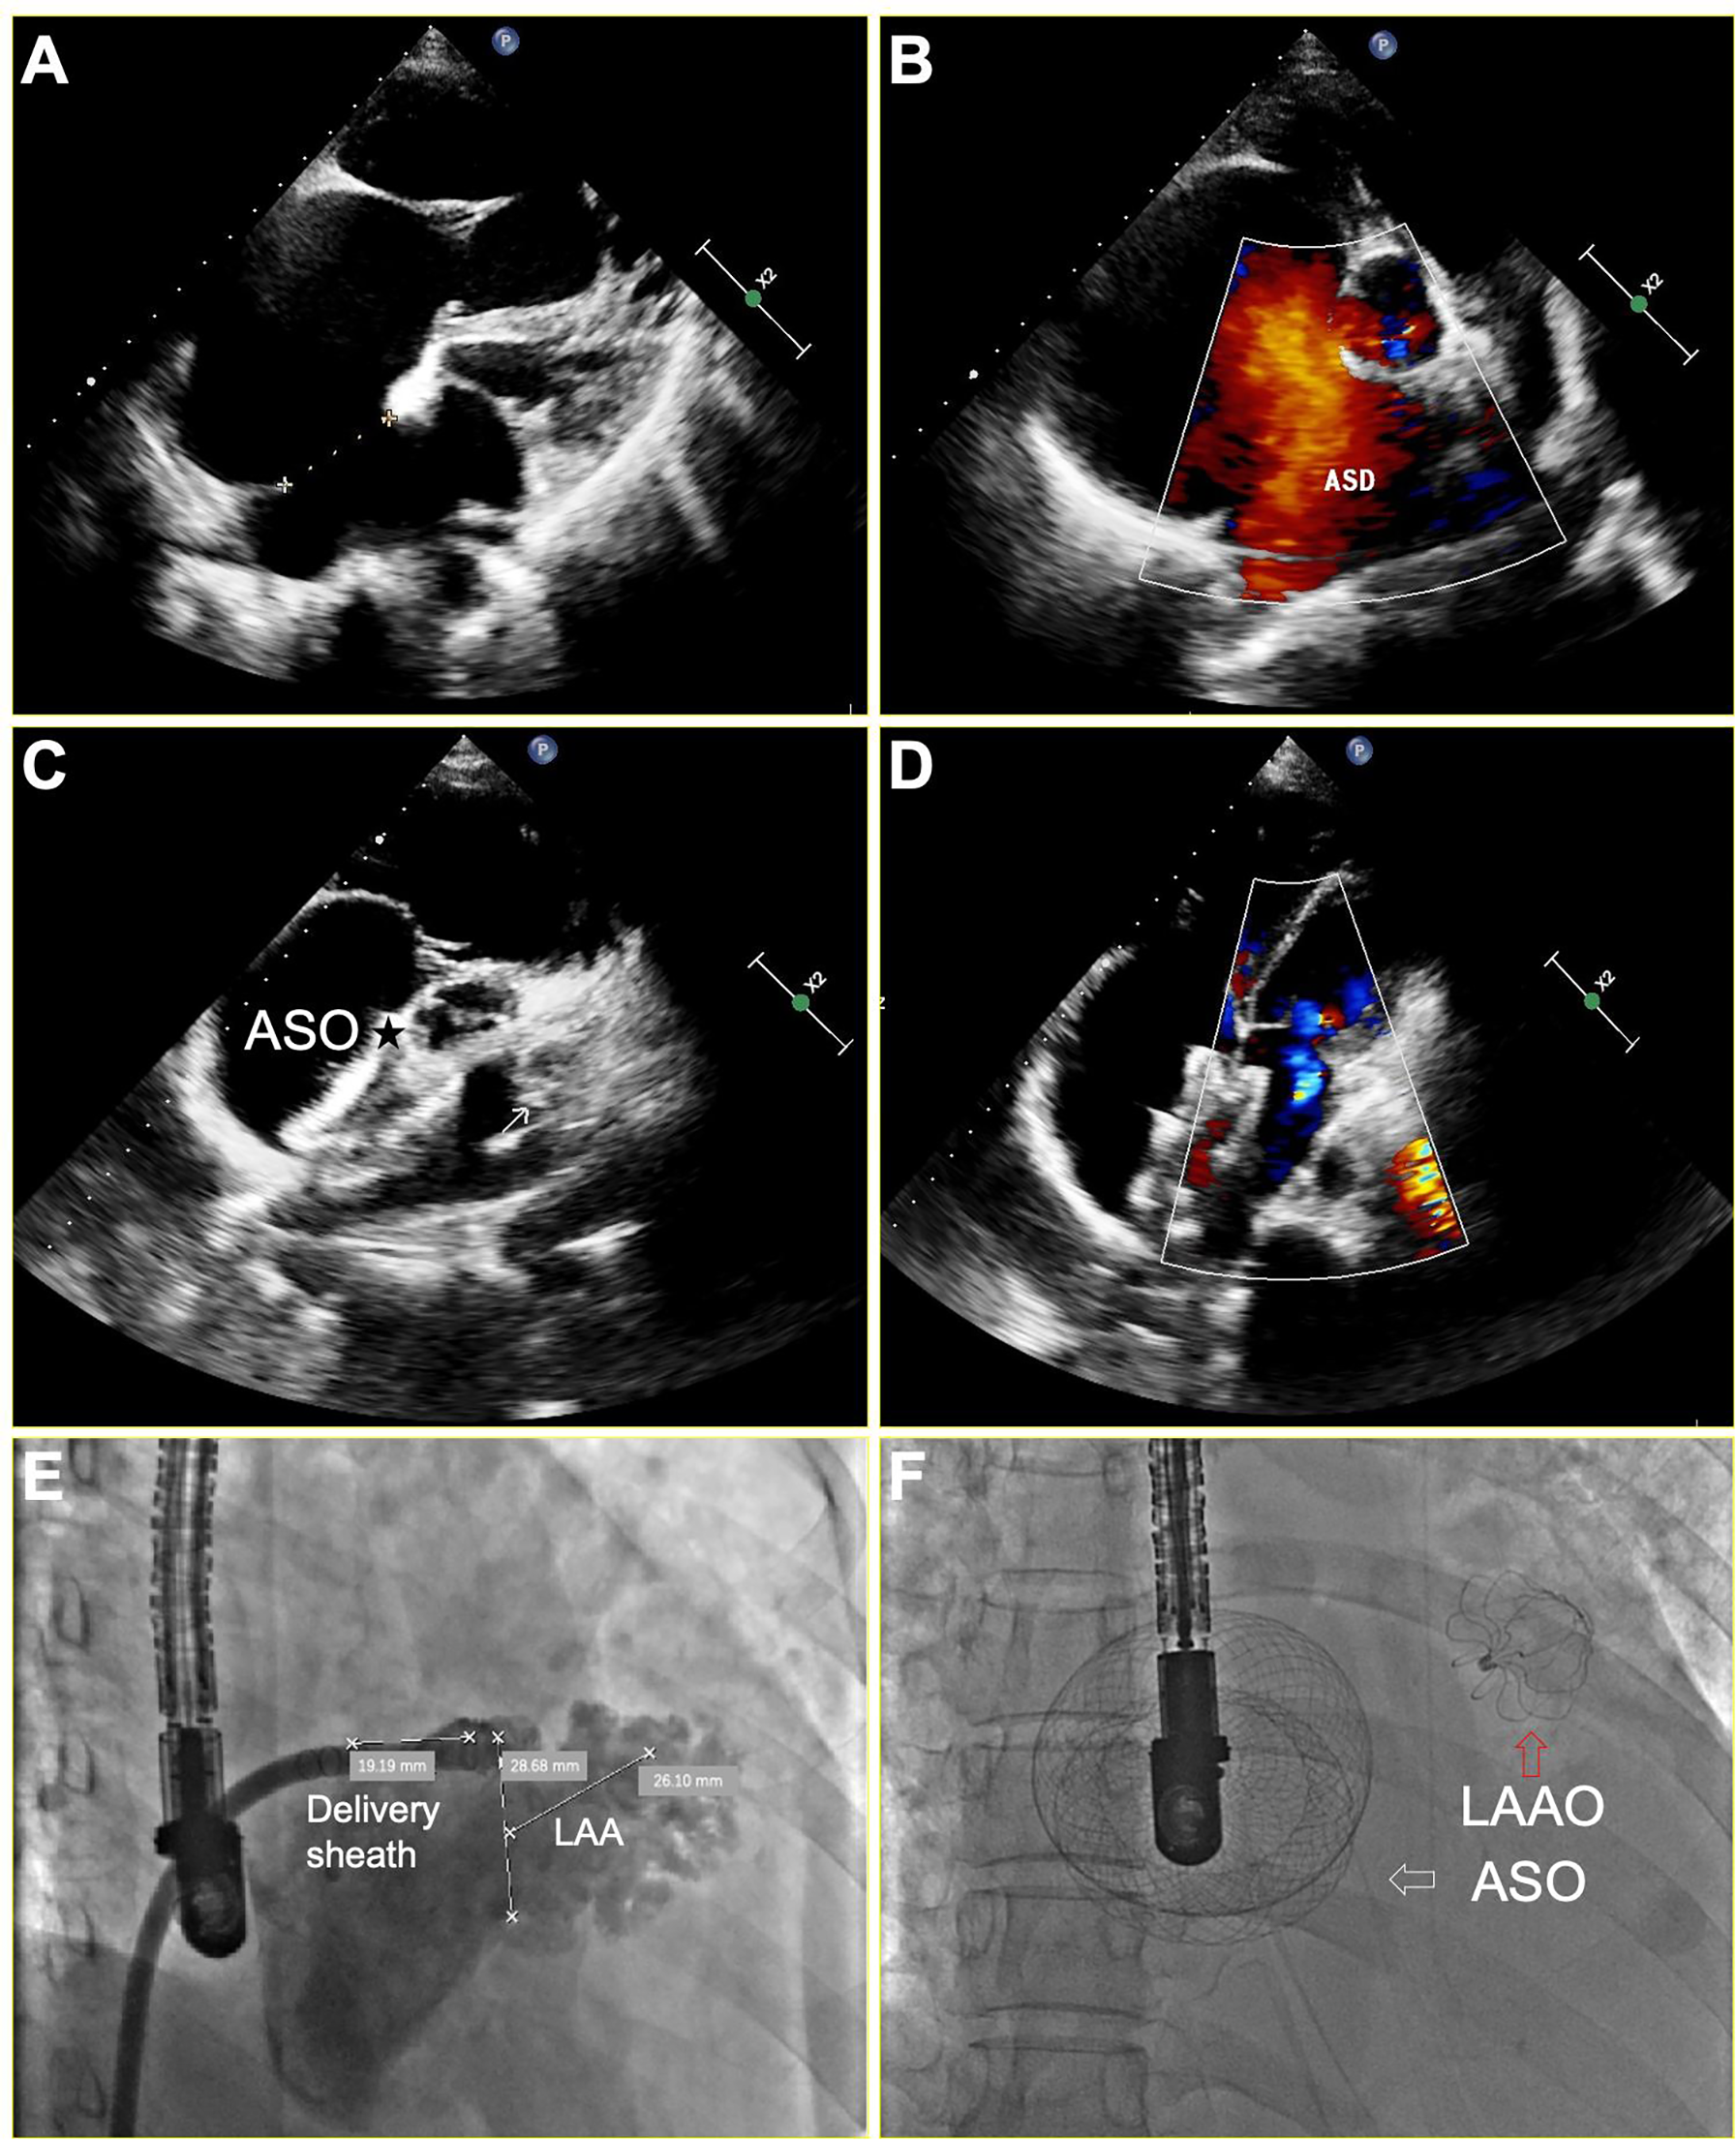

The right femoral vein was punctured under local anesthesia, then right and left heart catheterization was performed to measure the pressure of pulmonary artery, right ventricle, right atrium and left atrium. Pulmonary vascular resistance (PVR) and pulmonary to systemic blood flow (Qp/Qs) ratio were calculated by the Fick equation (7). Once the patient met the indications for closing ASD as previously described (5), general anesthesia was given to perform the following one-stop procedure. The transesophageal echocardiogram (TEE) was performed to assess the presence of thrombi in LAA and measure the size and length of LAA at 0°, 45°, 90°, and 135°. The LAA was closed via conventional method using a WATCHMAN (Boston Scientific, MA, USA) or LAmbre (Xianjian Technology Co., Shenzhen, China) device. The details regarding LAAC and characteristics of devices were as previously described (8, 9). After successful closure of the LAA, subsequent occlusion of the ASD was performed as previously described (1). Two devices were used: the SHSMA ASD occluder (Shape Memory Alloy Co., shanghai, China), and the Amplatzer ASD occluder (St. Jude Medical, Golden Valley, MN). Figure 1 depicts concurrent LAAC with the WATCHMAN™ device and ASD occlusion under TEE guidance in a patient with persistent AF and ASD.

Figure 1

TEE and x-ray imaging of successful LAA and ASD occlusion for a patient with persistent AF and a larger ASD. (A,B) ASD measuring 33 mm in diameter, resulting in a significant left-to-right shunt in the color-Doppler analysis; (C,D) Disappearance of complete shunt after a 46 mm ASD occlusion device (asterisk) implantation; (E) A fluoroscopic illustration of the LAA positions and shapes before operation. (F) A fluoroscopic illustration of successful LAAC and ASD occlusion, white arrow indicates the ASO, while red arrow indicates the LAAO. ASD, atrial septal defect; ASO, atrial septal occluder; LAAO, left atrial appendage occluder.